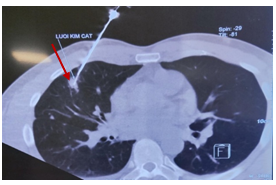

Đến 6 tháng sau bệnh nhân đi khám sức khoẻ được chụp cắt lớp vi tính lồng ngực cho kết quả: Vài nốt đặc thùy giữa và dưới phổi phải, nốt lớn kích thước 10x25mm, tràn dịch màng phổi phải => vào Trung tâm Y học hạt nhân và Ung bướu đánh giá và điều trị

Hình 1: Hình ảnh cắt lớp vi tính lồng ngực: nốt tổn thương u phổi phải kích thước 10x25mm (mũi tên đỏ), dịch màng phổi phải (mũi tên vàng), tổn thương di căn phổi (mũi tên xanh)